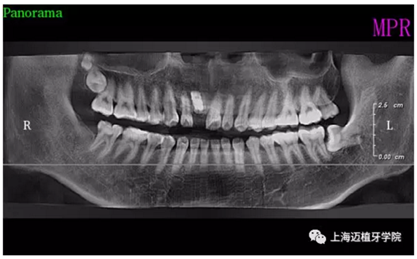

術(shù)前全景片

主訴:前門(mén)外傷牙根折要求修復(fù)?現(xiàn)病史:前門(mén)牙外傷,劈裂至根部,無(wú)法固定及其他修復(fù),要求種植?檢查:11牙冠2/3缺損,唇腭向劈裂,唇部紅腫。 CT示根折, 骨寬度9.47mm,距鼻底12.34mm,Ⅲ類骨。 口腔衛(wèi)生一般